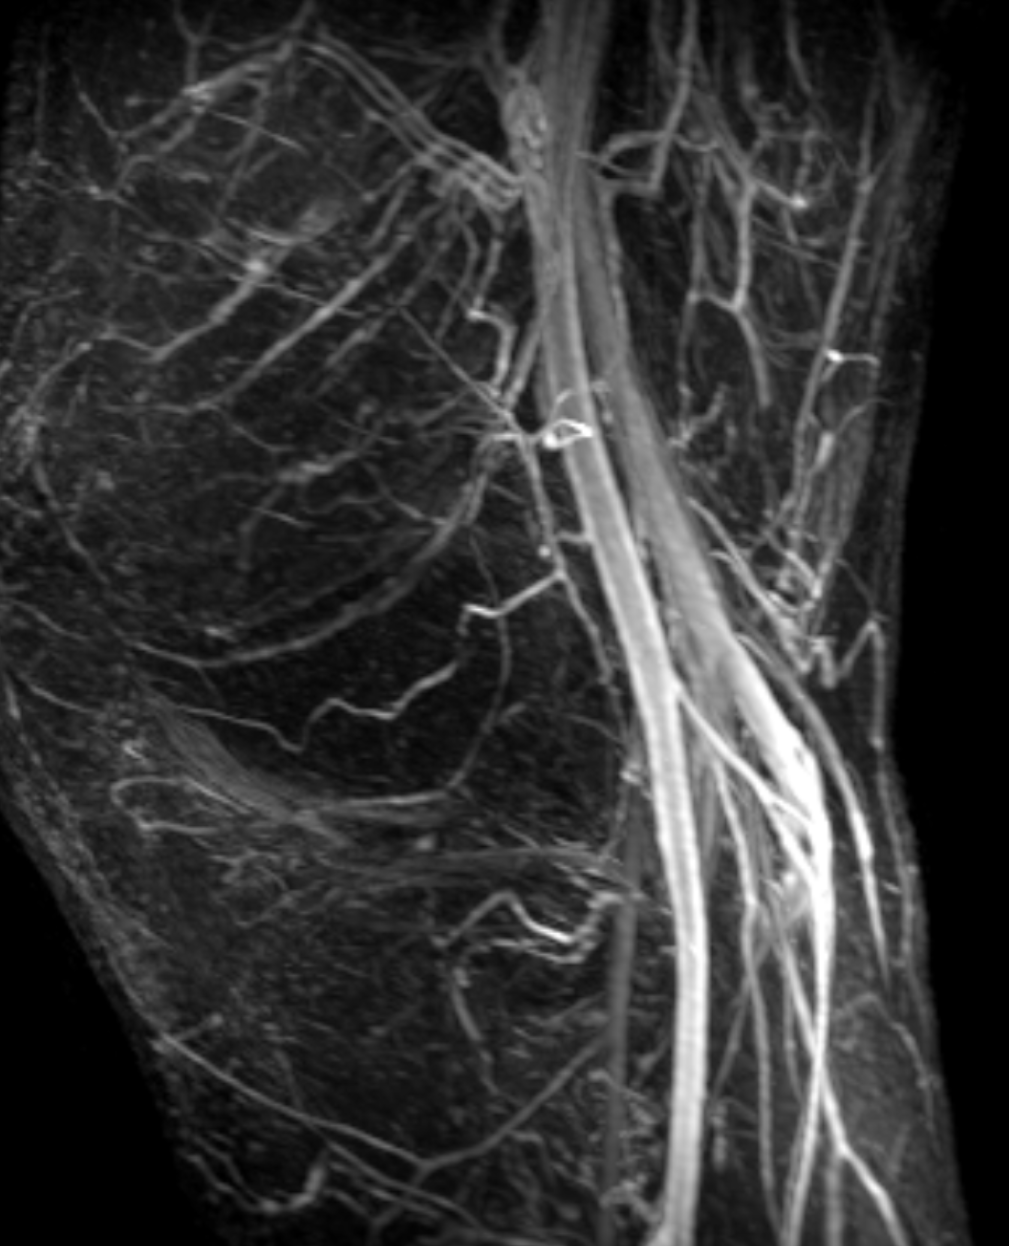

unanimity was: it is a *ganglion cyst,* nobody ever saw a vascular

malformation inside ACL

I did an CE MRangiography, and indeed, the structure inside LIA did not

enhance internally, only the linining, which is consistent with a ganglion

cyst.

The serpigionous part enhances – but not like a vessel (because on

angiographic phases is not seen). It is probable just the internal lining

enhancement (so small caliper of the structure) which is a bit late.